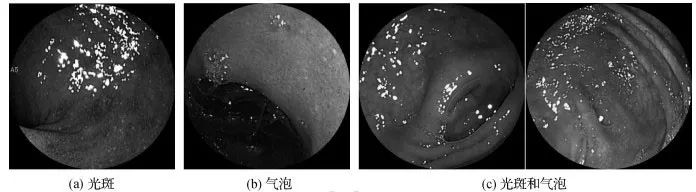

压缩感知下溃疡性结肠炎辅助诊断

作者:杨海清,孙道洋

第一作者单位:浙江工业大学信息工程学院

关键词:溃疡性结肠炎; 计算机辅助诊断; 压缩感知; 交替优化; 空间金字塔池化